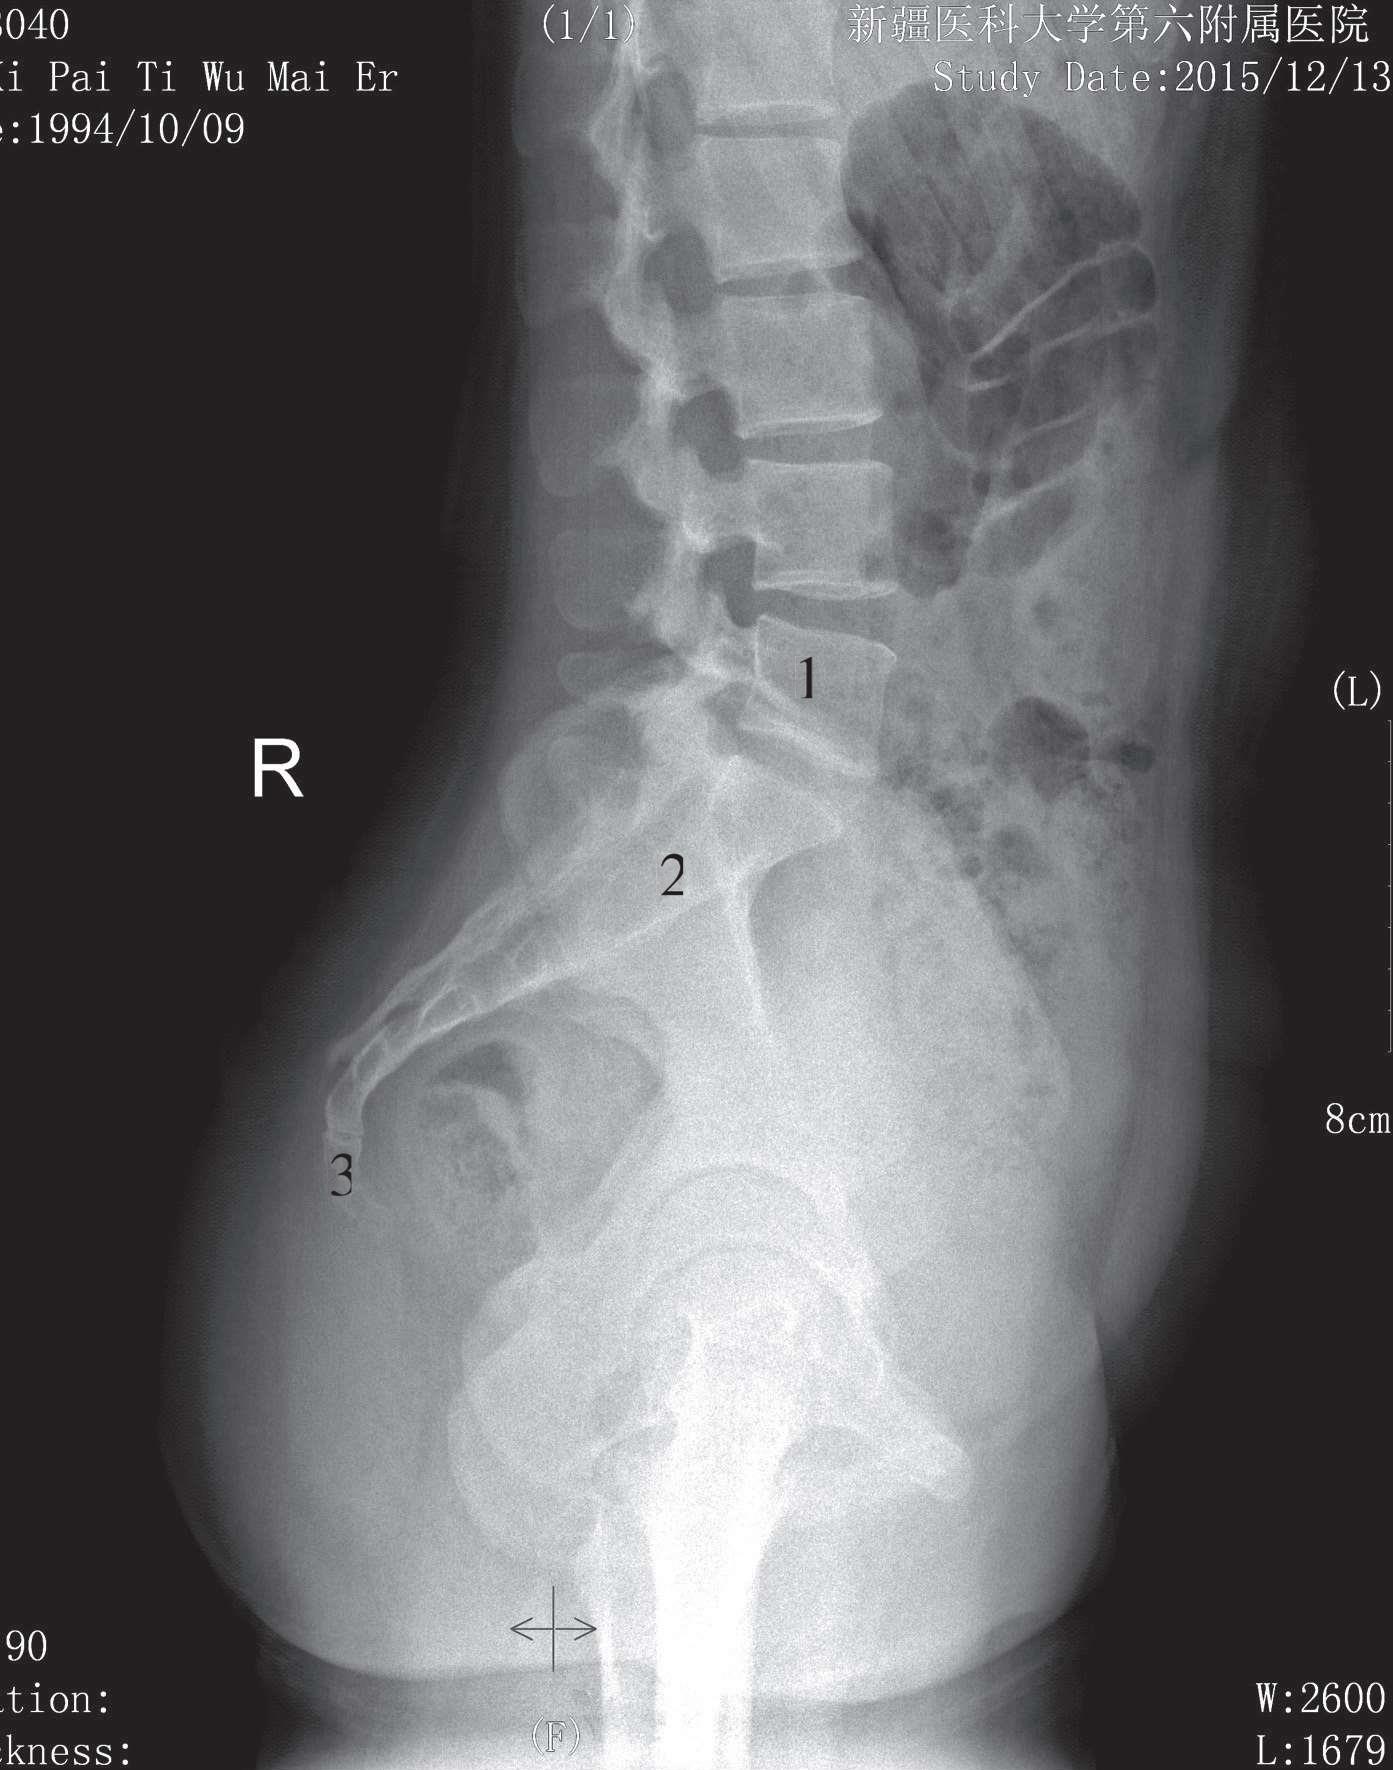

被检者侧卧于检查床上,两臂上举抱头,双下肢屈曲,身体正中矢状面与床面平行,影像接收器上缘包括T 11 ,下缘包括上部骶椎,中心线对准L 3 垂直射入。影像显示腰椎生理性前凸,椎弓根、椎间孔、椎间关节及棘突显示清晰,椎间隙较正位片显示清晰,骨皮质及骨小梁显示良好(图3-14)。

1. 椎体;2. 椎间隙;3. 棘突;4. 下关节突;5. 上关节突

图3-14 腰椎侧位片